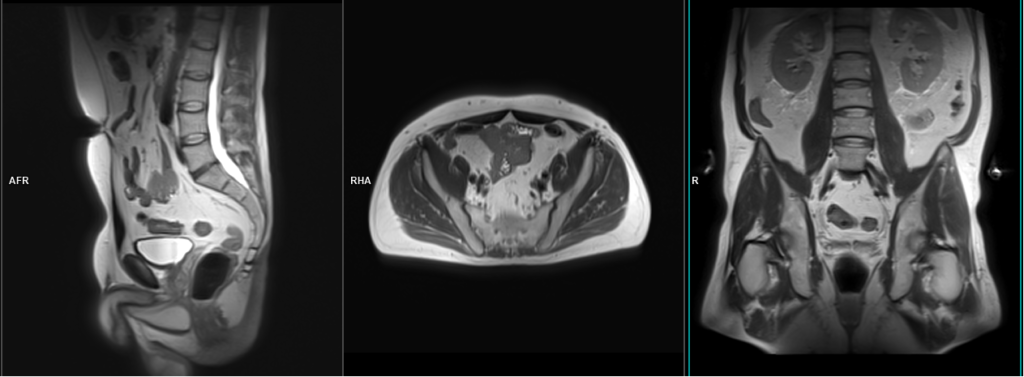

T2 tse sagittal 3mm SFOV prostate

Plan the sagittal slices on the axial plane, angling the positioning block parallel to the interpubic fibrocartilage and the anal canal. Check the positioning block in the other two planes, ensuring an appropriate angle is given in the coronal plane (parallel to the interpubic fibrocartilage). The slices must be sufficient to cover the entire pelvis from the right acetabulum to the left acetabulum. The field of view (FOV) must be large enough to encompass the prostate and seminal vesicles (typically 180mm-200mm). Additionally, to minimize artifacts arising from arterial pulsation, peristalsis, and breathing, consider incorporating saturation bands on the top and front of the sagittal block.

T2 tse axial 3mm SFOV prostate (straight axial)

Plan the axial slices on the sagittal plane; angle the positioning block horizontally across the prostate (i.e., parallel to the base of the penis). Check the positioning block in the other two planes. An appropriate angle must be given in the coronal plane (parallel to the right and left femoral heads). Slices must be sufficient to cover the whole prostate and seminal vesicles. Additionally, to minimize artifacts arising from arterial pulsation, peristalsis, and breathing, consider incorporating saturation bands on top and in front of the axial block.

T2 tse coronal 3mm SFOV

Plan the coronal slices on the sagittal plane and angle the positioning block vertically across the prostate, as shown in the picture. Check the positioning block in the other two planes, ensuring an appropriate angle is given in the axial plane (parallel to the right and left hip joints or ischial tuberosity). The slices must be sufficient to cover the entire prostate and seminal vesicles. Additionally, to minimize artifacts stemming from arterial pulsation and breathing, consider incorporating saturation bands on the top and front of the coronal block.